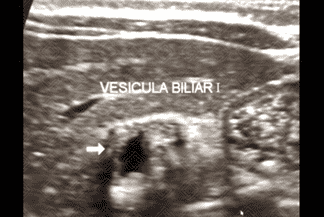

Texto alternativo para a imagem Figura 1. Créditos: Dra. Elazir Mota - Rio de Janeiro/RJ

Descrição da lesão: Atresia de vias biliares. Ultrassonografia do abdome evidenciando vesícula "atrésica" (eixo longitudinal < 15 mm e com contornos irregulares) (figuras 1 e 2), cordão hiperecogênico anterior à bifurcação da veia porta (figura 3), esplenomegalia e ascite (figura 4).

• Alteração na morfologia da vesícula biliar (VB): 1. Presença ou ausência de VB; 2. Dimensões da VB (diâmetro no eixo longitudinal inferior a 15 mm sugere VB atrésica, se > 15 mm é necessário avaliar sua morfologia); 3. Morfologia da VB (contorno regular ou irregular, presença ou ausência da mucosa regular hiperecogênica em toda extensão da VB);